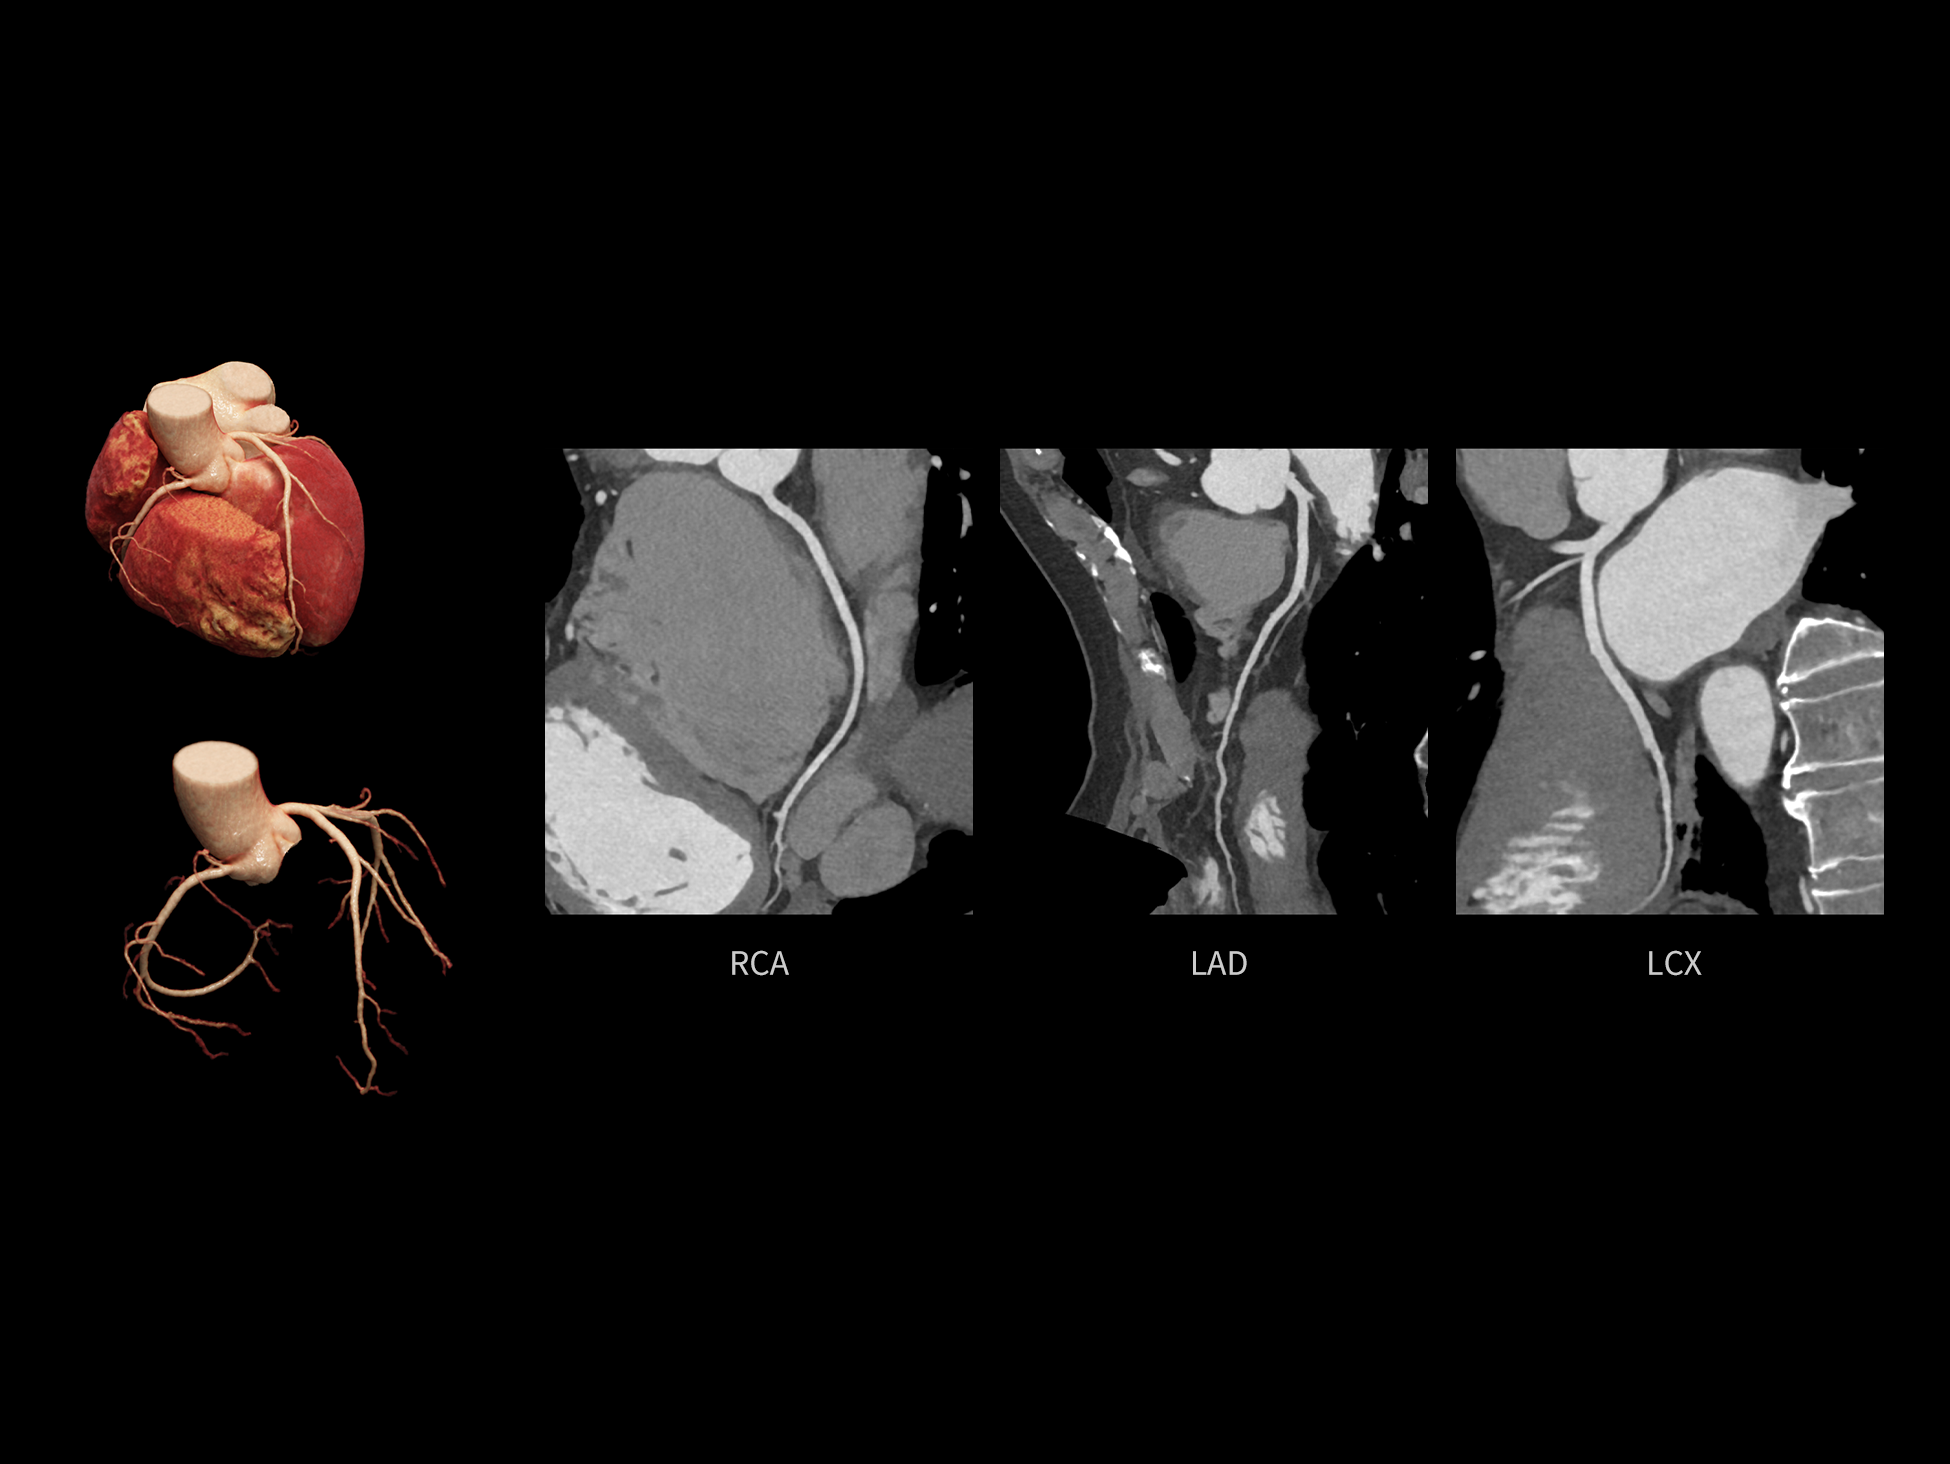

全时心脏

uCT SiriuX® 挑战心脏成像时间分辨率的极限,精准捕捉心脏全周期的动态变化。无论静态解剖形态,还是动态功能表现,都能清晰呈现,让心脏不再是“定格”的器官,而成为可视的生命律动。

CardioCapture 2.0 通过“识别–追踪–建模–校正”的完整流程,精准分割心脏结构,动态追踪运动轨迹,并构建多时相运动场,最终实现冠脉、瓣膜、心肌及心室结构的同步校正,清晰洞见每一次心跳细微变化,真正将心脏动态掌握于毫秒之间。

CardioCapture 2.0 在目标时相前后重建多时相影像,通过深度学习网络精准提取冠脉中心线,进而建立时相间运动模型,实现对冠脉分段图像的精准运动校正。

CardioCapture 2.0 可对心肌、瓣膜及心室等结构进行同步运动校正。基于深度学习的心脏精细分割,实现了更完整的心脏全局信息提取,能有效抑制全心运动伪影,显著提升心脏细节的清晰度与诊断可靠性。

8ms 全心等效时间分辨率

冠脉运动校正

全心结构运动校正

心脏成像,自由掌控